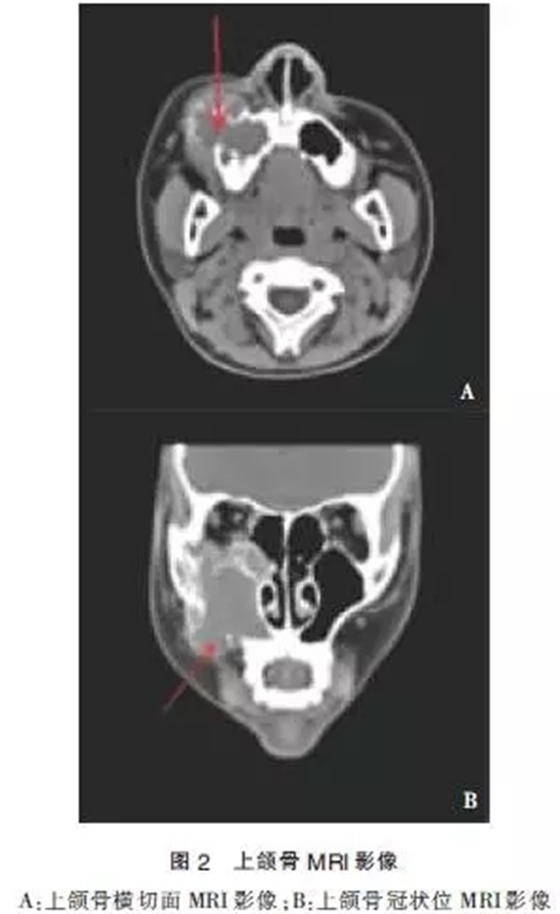

患者于2014-03-14行MRI檢查示:右側(cè)上頜竇為中心,右側(cè)眶下壁至上頜骨區(qū)頜面部可見(jiàn)一不規(guī)則形軟組織信號(hào)腫塊影,大小約4.2 cm×4.7cm×5.9cm。輪廓不光整,病灶可見(jiàn)斑點(diǎn)狀,棒狀短T1高信號(hào),短T2低信號(hào)影,輪廓清晰。病灶部分突入右側(cè)鼻腔內(nèi),鼻中隔居中,注射造影劑后上述病灶呈不均勻顯著異常強(qiáng)化,右側(cè)額竇、篩竇及蝶竇內(nèi)可見(jiàn)長(zhǎng)T2高信號(hào)影。

影像學(xué)診斷:①右側(cè)頜面部占位,血管瘤或惡性腫瘤可能;②垂體形態(tài)不規(guī)則,請(qǐng)結(jié)合臨床考慮(圖2)。于2014-03-18行“頸內(nèi)外動(dòng)脈造影+血管瘤供血?jiǎng)用}栓塞術(shù)”,患者仰臥,心電監(jiān)護(hù)下,常規(guī)右腹股溝消毒,鋪無(wú)菌巾,2%利多卡因局麻后,以技術(shù)穿刺右股動(dòng)脈,置入5F鞘管送5F單彎導(dǎo)管分別選擇性進(jìn)入兩側(cè)頸動(dòng)脈。右側(cè)頸內(nèi)外動(dòng)脈造影(圖3):右側(cè)頜面部可見(jiàn)富血供染色病灶,呈現(xiàn)“血管湖”徑,右側(cè)頜內(nèi)動(dòng)脈為主要供血?jiǎng)用},參與約80%供血,右側(cè)面動(dòng)脈及顳淺動(dòng)脈分支參與約10%供血,右側(cè)眼動(dòng)脈分支參與約10%供血,左側(cè)頸內(nèi)動(dòng)脈及各大腦動(dòng)脈及其分支顯影清晰,未見(jiàn)明顯異常。